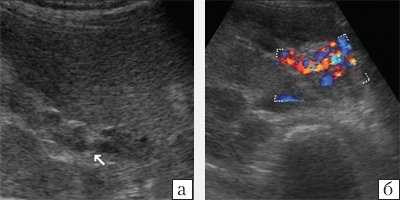

При ультразвуковом исследовании (УЗИ) в серошкальном режиме в просвете воротной вены можно выявить неоднородное образование повышенной или смешанной эхогенности, с неровными, нечеткими контурами, препятствующее кровотоку, размеры которого могут быть различными: от 0,5 см до полной окклюзии воротной вены и/или ее ветвей (рис. 1, а). Эхогенность тромба чаще является более высокой, чем окружающей его крови. Однако на ранних стадиях формирования эхогенность может отличаться настолько незначительно, что визуализация тромба чрезвычайно сложна. Могут определяться увеличение диаметра сосуда с нечеткостью контуров, увеличение печени и снижение ее эхогенности, увеличение селезенки. Могут быть найдены первопричины тромбоза воротной вены: гепатоцеллюлярная карцинома, метастазы, цирроз печени, новообразования поджелудочной железы и др. При пилефлебите обнаруживают абсцессы печени [3].

a) В-режим. Неоднородное образование повышенной эхогенности с неровными, нечеткими контурами в просвете воротной вены (стрелки).

б) Режим ЦДК. Полное отсутствие допплеровских сигналов внутри просвета сосуда; допплеровский сигнал определяется в сети мелких коллатералей.